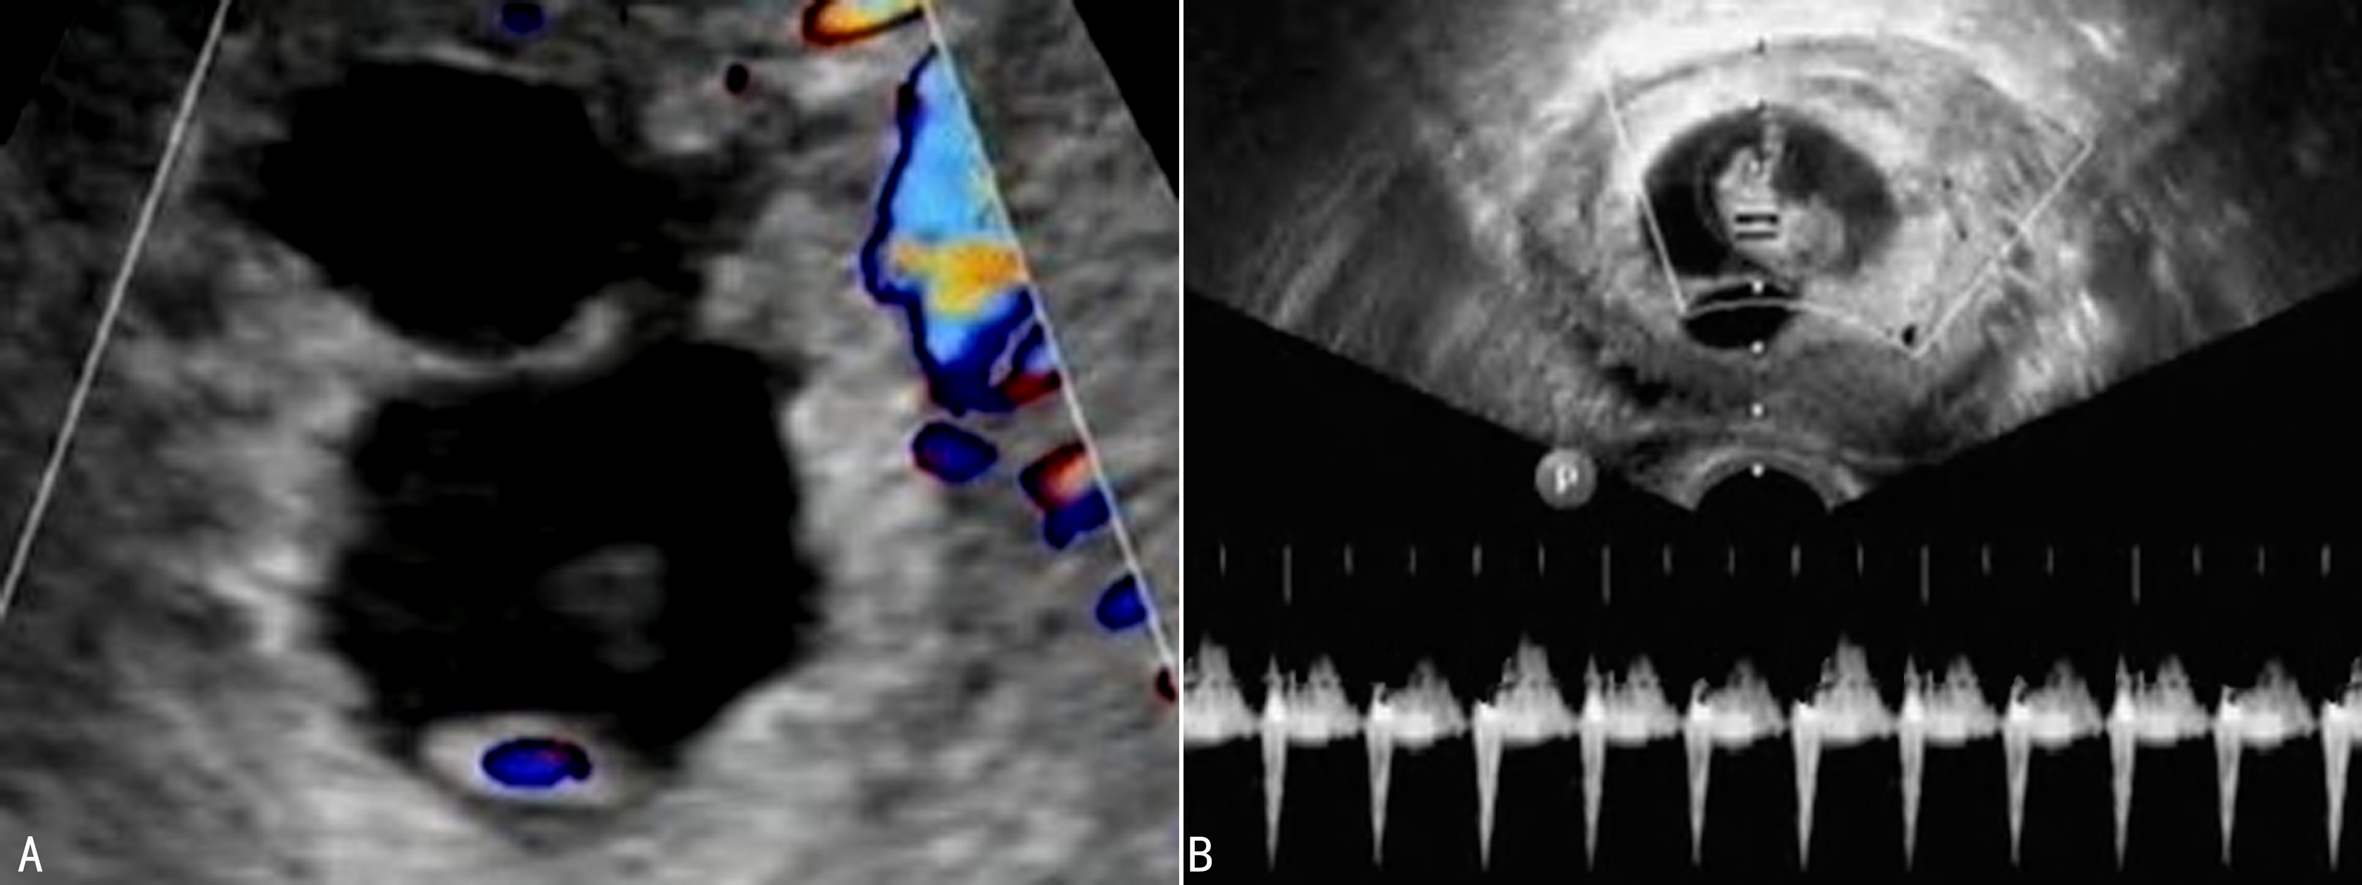

(四)胎盘-脐带超声多普勒检查

多胎妊娠中胎盘脐带循环的差异可以引起胎儿发育的不平衡。胎盘-脐带循环的超声多普检查有助于对胎儿宫内发育迟缓或胎儿发育不一致的评估。脐带血流S/D增加和羊水量、羊水物理性状改变及新生儿Apgar评分的降低有一定的关系。双胎妊娠产前超声检查中超声多普勒可用于涉及胎儿血流动力学和胎盘循环的并发症检查中,不建议将超声多普勒检查作为常规胎儿超声检查方法。